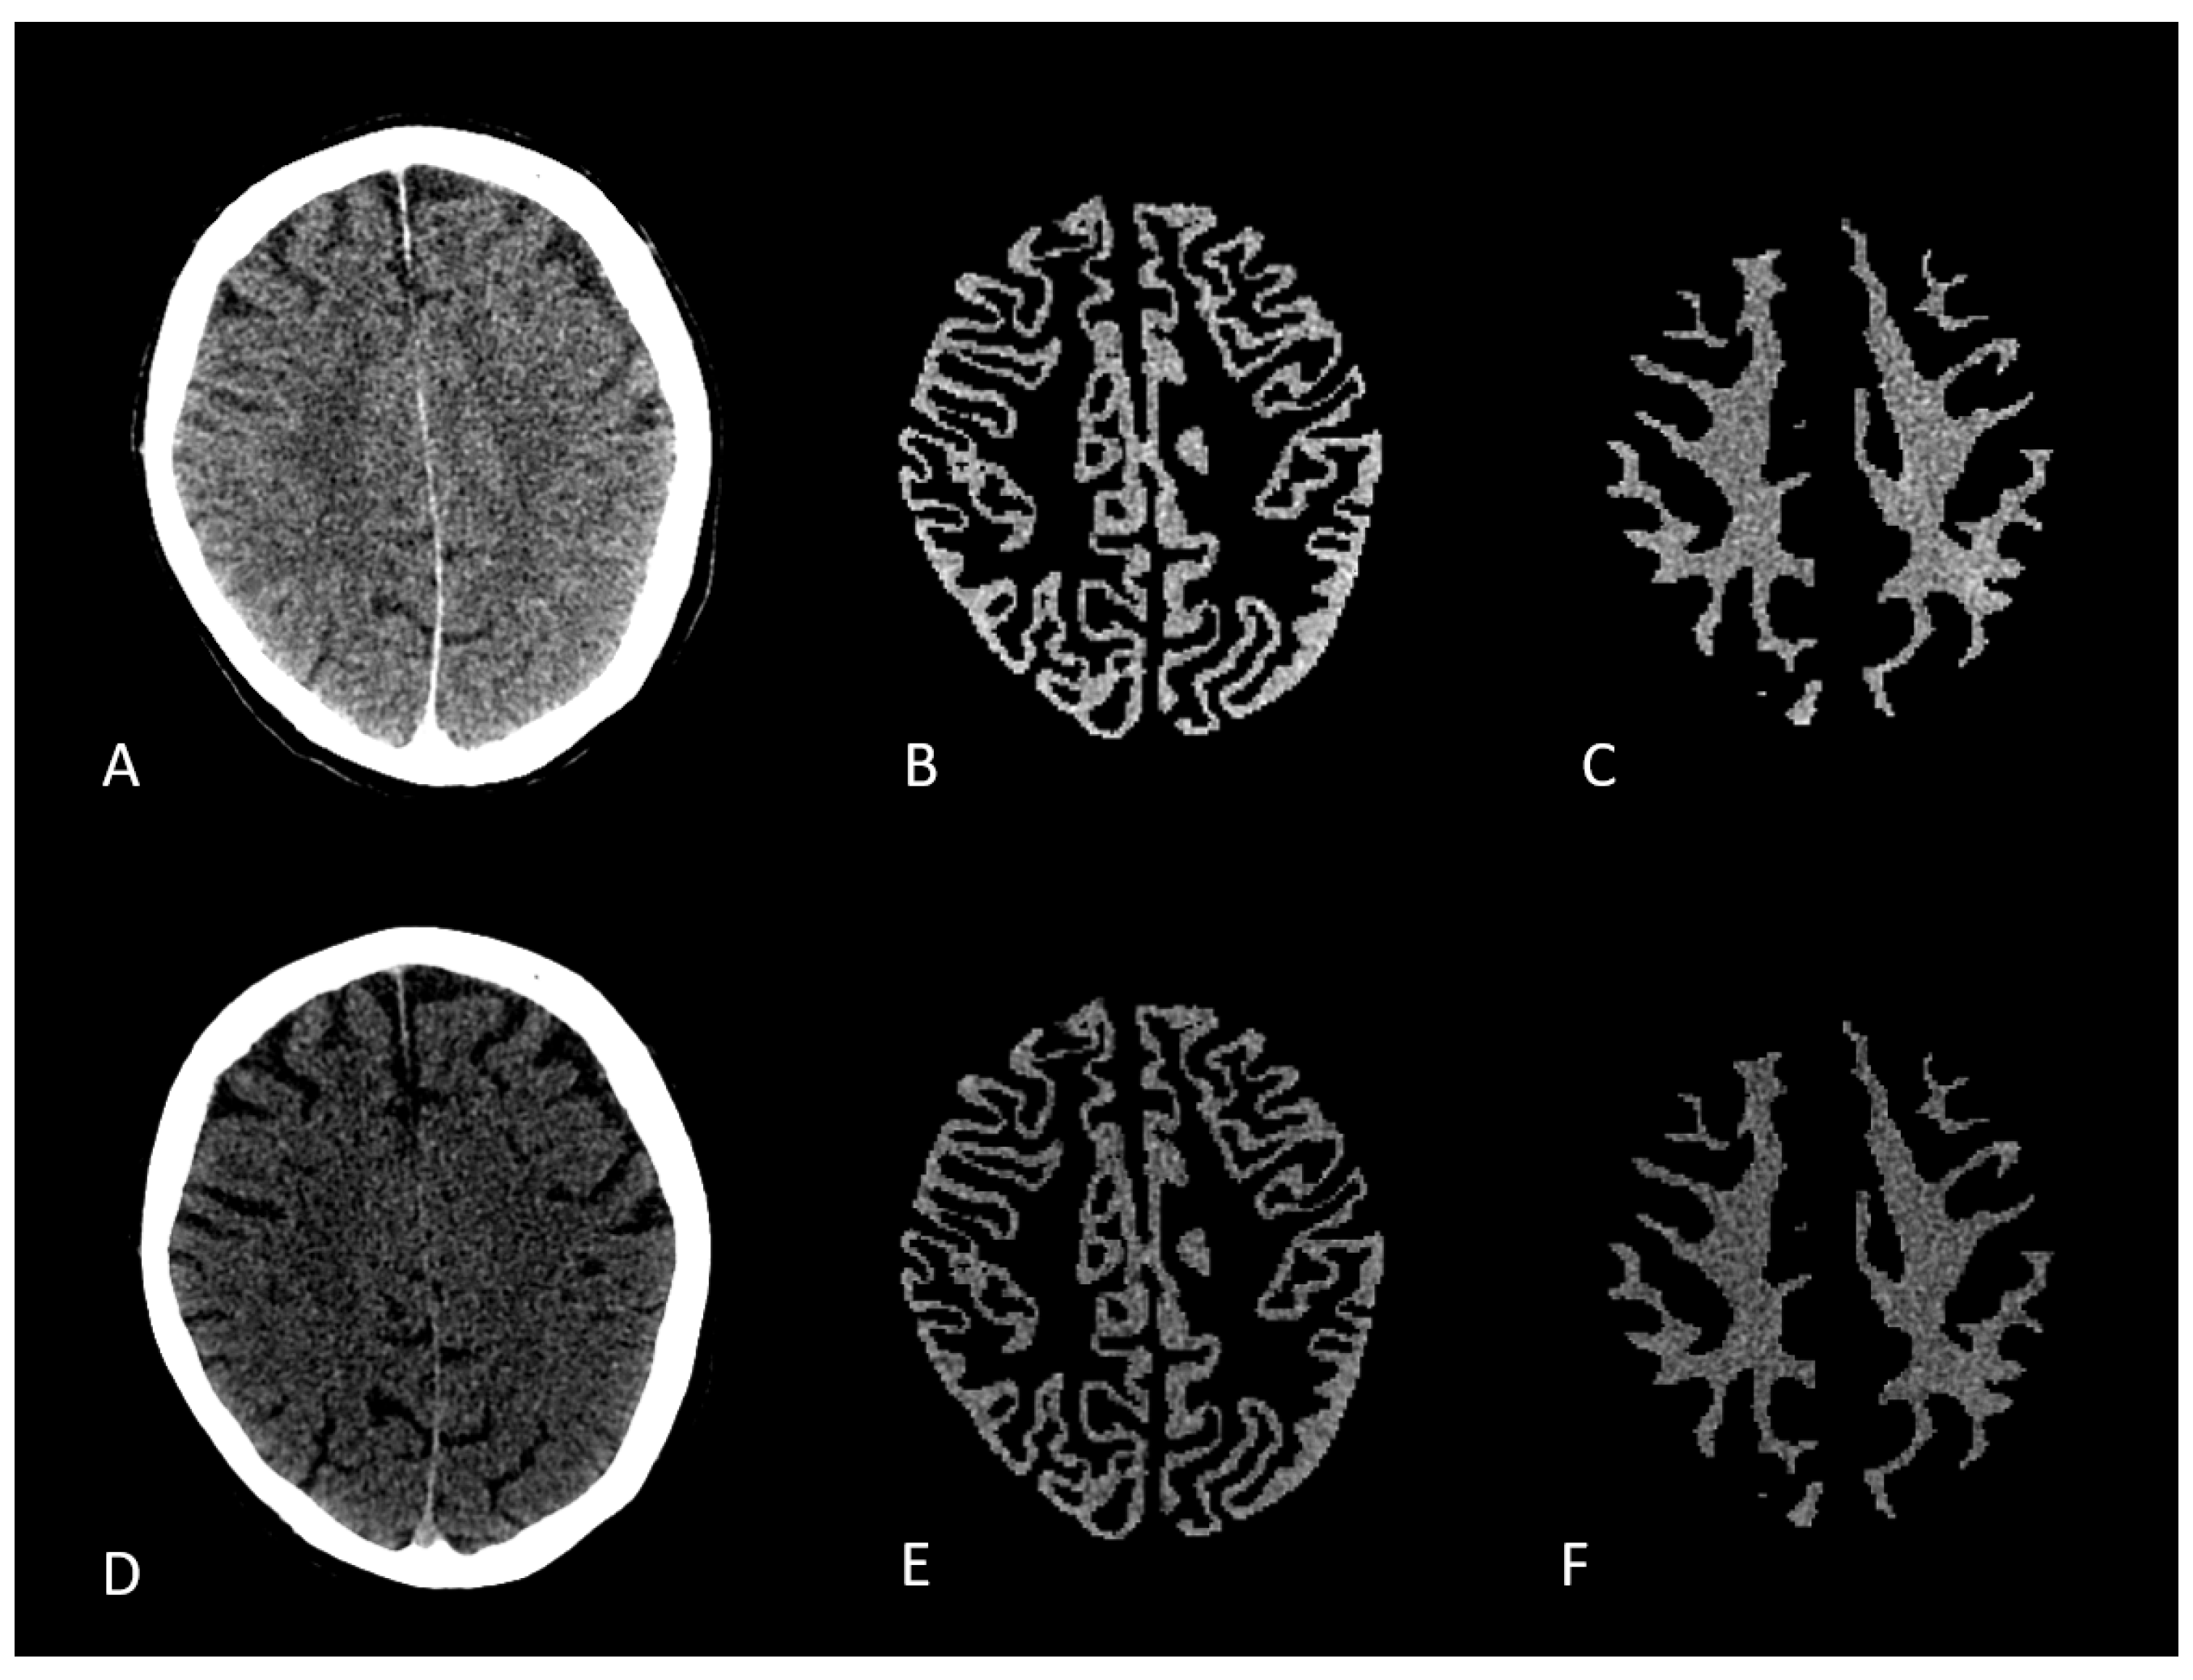

Mixed, low and high energy datasets of the Dual Energy CT were converted to nifti format. The mixed energy series was then converted into a synthetic MPRAGE using SynthSR convolutional neural network (CNN).[18] Synthetic MPRAGE was then segmented into gray and white matter using SPM12. Segmentation files were registered and overlaid onto low- and high-energy CT scans. Voxel based Hounsfield units of gray and white matter were measured using Python. [19] Figure 1.

Figure 1. A/B/C: 80 kV CT scan with respective GM and WM segmentation masks; D/E/F: sn150 kV scan with respective GM and WM segmentation masks